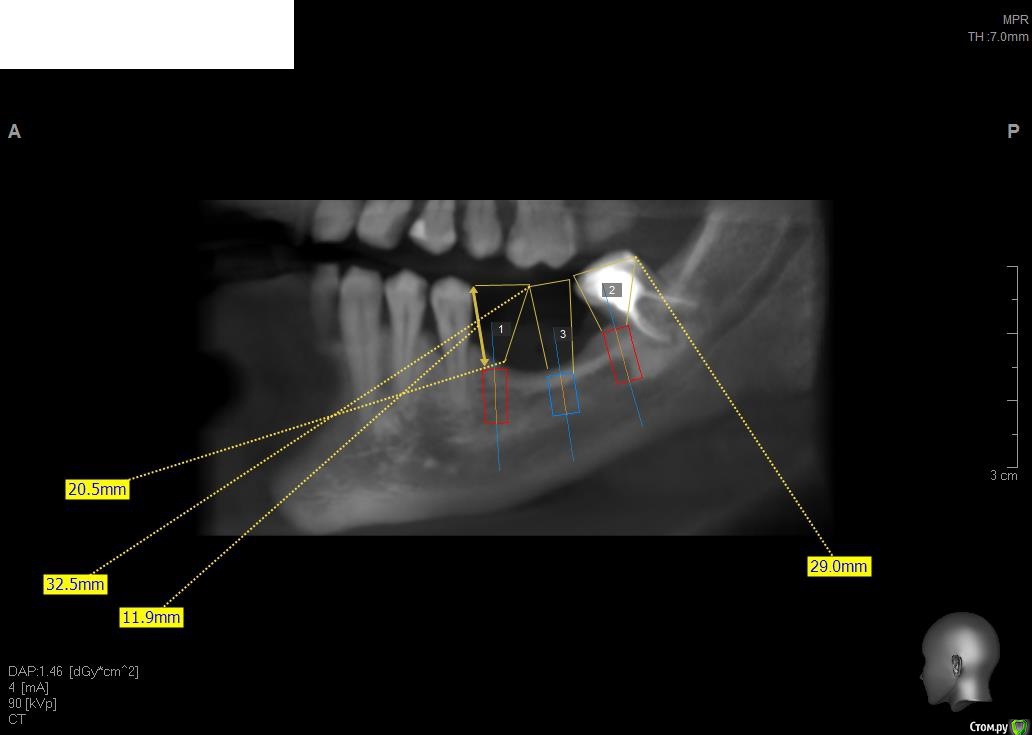

Павел7809 Опубликовано 21 ноября, 2017 Поделиться Опубликовано 21 ноября, 2017 Здравствуйте коллеги! Собственно ситуация на скринах. Для сосиджа как то экстремально большой объем. Блоки? Сетка?(ох как не хочется! последняя развалилась....) Крыша гаража? Из инструментария есть абсолютно все... Ссылка на комментарий

Павел7809 Опубликовано 21 ноября, 2017 Автор Поделиться Опубликовано 21 ноября, 2017 Коротышки с десной не рассматриваете? с удалением 8киинтересная идея...в принципе 2 астры туда влезают 4 на 6, боюсь просто эстетически получится некрасиво Ссылка на комментарий

Павел7809 Опубликовано 21 ноября, 2017 Автор Поделиться Опубликовано 21 ноября, 2017 Платформы имплантов будут на уровне апексов соседних зубов. Это будет эстетический ад. Ссылка на комментарий

Павел7809 Опубликовано 22 ноября, 2017 Автор Поделиться Опубликовано 22 ноября, 2017 (изменено) Да, но проблема в том , что на место 7 ки как бы и 6мм не влезает. Вообще мысль появилась поставить короткую 6 ку на месте 6 го зуба, удалить 8, поставить на его место имплант(там с местом проблемы нет, и сделать мостик) . Ну или сетка(ой как не хочется!) Мало того я посмотрел и понял что элементарно влезают восьмерки в обл 36 38 Изменено 22 ноября, 2017 пользователем Павел7809 1 Ссылка на комментарий

Павел7809 Опубликовано 25 ноября, 2017 Автор Поделиться Опубликовано 25 ноября, 2017 Пообщался с пациентом. Сошлись на коротышках 4 на 6 в область 7 ки, 9 на 4 в области 6 4ки. Да и по факту я посмотрел - коронки не будут такими уж огромными выглядеть. 1 Ссылка на комментарий